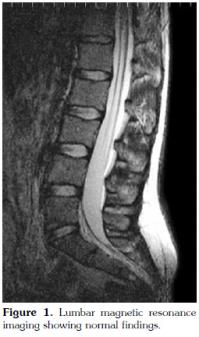

There were no abnormal findings of the lumbar spine on magnetic resonance imaging (MRI) (Figure 1). Contrast enhanced sacroiliac MRI revealed lobulated, multivesicular cystic lesions, which originated from the second sacral vertebra, extending to the sacral ala and iliac wing at the third sacral level, which also filled the sacroiliac joint. Vesicular lesions in the sacroiliac joint and piriform muscles showed increased contrast uptake (Figure 2). Given the patient's medical history, bone hydatid disease and other cystic bone lesions were included in differential diagnosis.

Furthermore, MRI usually helps to define features of the cyst except calcifications.[4] Hydatid cyst appears as well formed, thin-walled and spherical lesions on MRI.[10] The fluid of the cyst is isointense with cerebrospinal fluid both on T1 and T2-weighted images and the wall of the cyst appears as a low signal intensity rim. In defining the wall of the cyst, T2-weighted images are superior to T1-weighted images. Fluid has a high signal intensity and, in contrast, the wall of the cyst has a low signal intensity on T2-weighted images.[1] After intravenous contrast agent administration, the rim of the cyst shows no uptake. Calcification of the cysts wall is a very rare entity.[11] Computed tomography images resemble T1-weighted MRI images. Magnetic resonance imaging of our patient revealed characteristics of hydatid cyst. Regular, thin-walled cyst and pericystic contrast uptake was determined. Chronic osteomyelitis, fibrous dysplasia of bone osteosarcoma, benign cystic lesions of the bone, brown tumor (hyperparathyroidism), and neoplastic lesions all should be included in the differential diagnosis.[12,13] Localization of lesions is also important. Although our patient did not present with inflammatory back pain, she had a presumptive diagnosis of AS and was medically treated for two years. This caused a delay in the diagnosis and unnecessary use of medication. Hence, atypical presentation of hip or low back pain and its irresponsiveness to anti-inflammatory medication warrants further investigation.